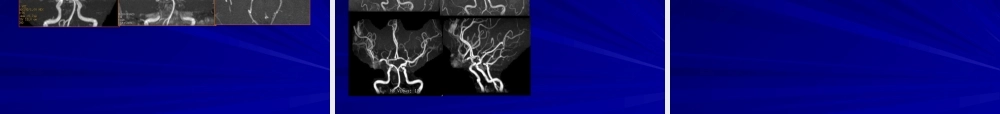

磁共振血管(xuèguǎn)成像(MRA)磁共振血管(xuèguǎn)成像(MRA)MR血管成像(MRangiographyMRA)是利用MR成像技术来描绘解剖组织中血管路径的方法。一般分为:时间(shíjiān)飞跃法(timeofflyTOF);相位对比(phasecontrastPC);对比增强MRA(CE-MRA)。磁共振血管(xuèguǎn)成像(MRA)时间飞跃法(timeofflyTOF)及相位对比(PCMRA)属于不需使用造影剂进行相关成像的技术(jìshù)。磁共振血管成像,是指利用血液流动的磁共振成像特点,对血管和血流信号特征显示的一种无创造影技术(jìshù),是基于GE(梯度回波)序列。对比增强MRA(CE-MRA)是利用顺磁性物质缩短血液T1的磁共振血管成像技术,属于造影剂增强MRA。临床应用最多的是TOF技术及CE-MRA技术,结合我科实际,也是我科重点推广的检查技术。PC是GRE序列,利用血流速度不同(bùtónɡ)引起的相位改变来区分流动和静止的质子。1、PhaseContrast•PC利用双极梯度(tīdù)采集图像+++++000000正相双极梯度-----000000负相双极梯度PC在重建血管(xuèguǎn)时用两次采集相减•静止质子被减去而流动质子保留MRA成像原理磁共振血管(xuèguǎn)成像(MRA)2.TOFMRATOF成像技术是基于血管的流入增强(zēngqiáng)效应,是指静止组织使用梯度回波序列经过连续多次的激励后静止组织处于稳定饱和状态,信号很低或不产生信号;而流入成像层面的血液则由于流入性增强效应而表现出很亮的信号。由于脉冲间隔时间很短,静止组织反复被激发,纵向磁矩不能充分弛豫而处于饱和状态,信号很弱,呈灰黑色;血管内血液流动,采集MR信号时,如果血流速度足够快,成像容积内激发的饱和质子流出扫描层面外,而成像容积外完全磁化的自旋又称不饱和自旋流入扫描层面,纵向磁矩大,发出强信号呈白色,于是血管内外信号差别很大,使血管显影。临床可以进行二维及三维技术进行采集,即:2D-TOF及3D-TOF。TOF是利用GRE序列的流动补偿,依靠流入增强效应区分静止(jìngzhǐ)和流动的质子。Time-of-Flight(TOF)静止质子无位移(wèiyí)而被饱和,产生较少信号流动(liúdòng)质子运动而不被饱和,产生亮信号MRA成像原理TOF成像原理(yuánlǐ)—饱和带饱和(bǎohé)脉冲置于成像容积的流入方向上进入成像容积(róngjī)前的预饱和使血流在进入成像容积(róngjī)后发生饱和,不产生信号层面的编辑必须与血流的方向相对并尽可能垂直于血流的方向,减少层间饱和血管通过层面后质子不被饱和...